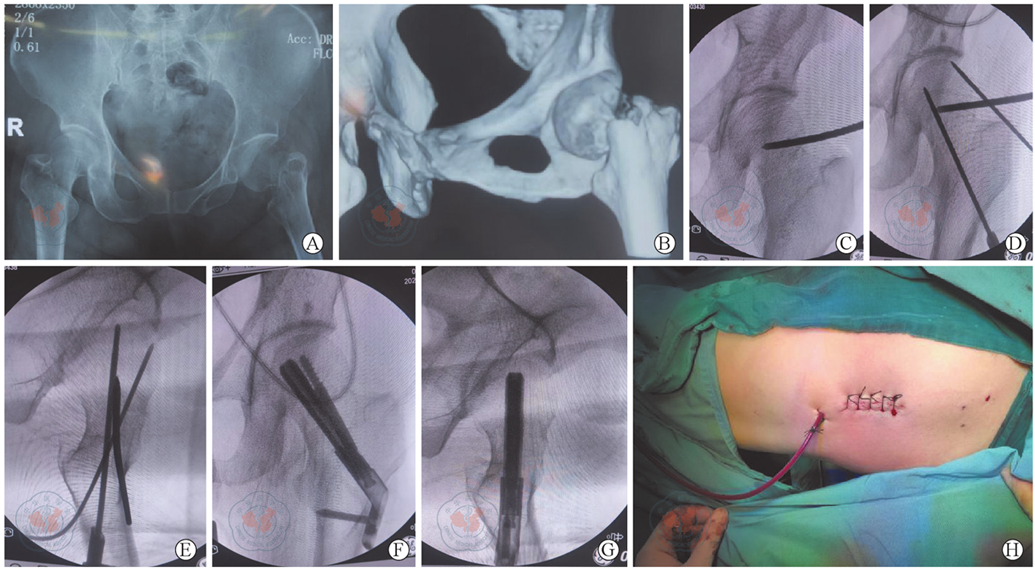

图1 Holosight机器人辅助FNS(股骨颈动力交叉钉系统)固定治疗右股骨颈骨折。图A为术前骨盆正位X线片,图B为术前CT三维重建,示右侧股骨颈骨折;图C为术中透视,示撬拨复位股骨颈骨折;图D~E为导航定位下置入导针;图F~G为术中透视,示置入股骨颈防旋系统;图H示手术切口已缝合

Figure 1 Holosight robot assisted FNS(femoral neck system) fixation for treatment of right femoral neck fracture. A is anteroposterior X-ray image of pelvis before surgery, B is three-dimensional reconstruction of CT image before surgery, showing right femoral neck fracture; C is fluoroscopy during surgery, showing leverage and reduction of femoral neck fractures; D and E are images showing that insertion of guide pins under navigation positioning; F and G are fluoroscopic images during surgery, showing the implantation of the femoral neck anti-rotation system; H shows the sutured surgical incision